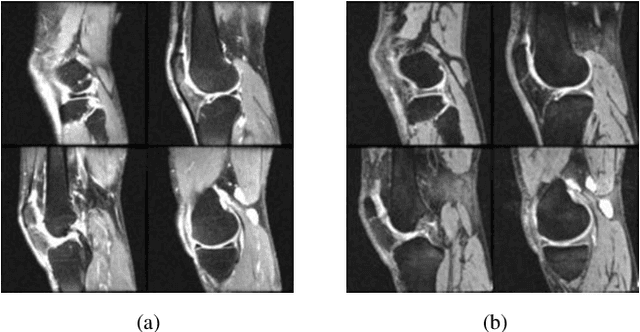

Abstract:Knee osteoarthritis (KOA) is a common joint disease that causes pain and mobility issues. While MRI-based deep learning models have demonstrated superior performance in predicting total knee replacement (TKR) and disease progression, their generalizability remains challenging, particularly when applied to imaging data from different sources. In this study, we have shown that replacing batch normalization with instance normalization, using data augmentation, and applying contrastive loss improves model generalization in a baseline deep learning model for knee osteoarthritis (KOA) prediction. We trained and evaluated our model using MRI data from the Osteoarthritis Initiative (OAI) database, considering sagittal fat-suppressed intermediate-weighted turbo spin-echo (FS-IW-TSE) images as the source domain and sagittal fat-suppressed three-dimensional (3D) dual-echo in steady state (DESS) images as the target domain. The results demonstrate a statistically significant improvement in classification accuracy across both domains, with our approach outperforming the baseline model.